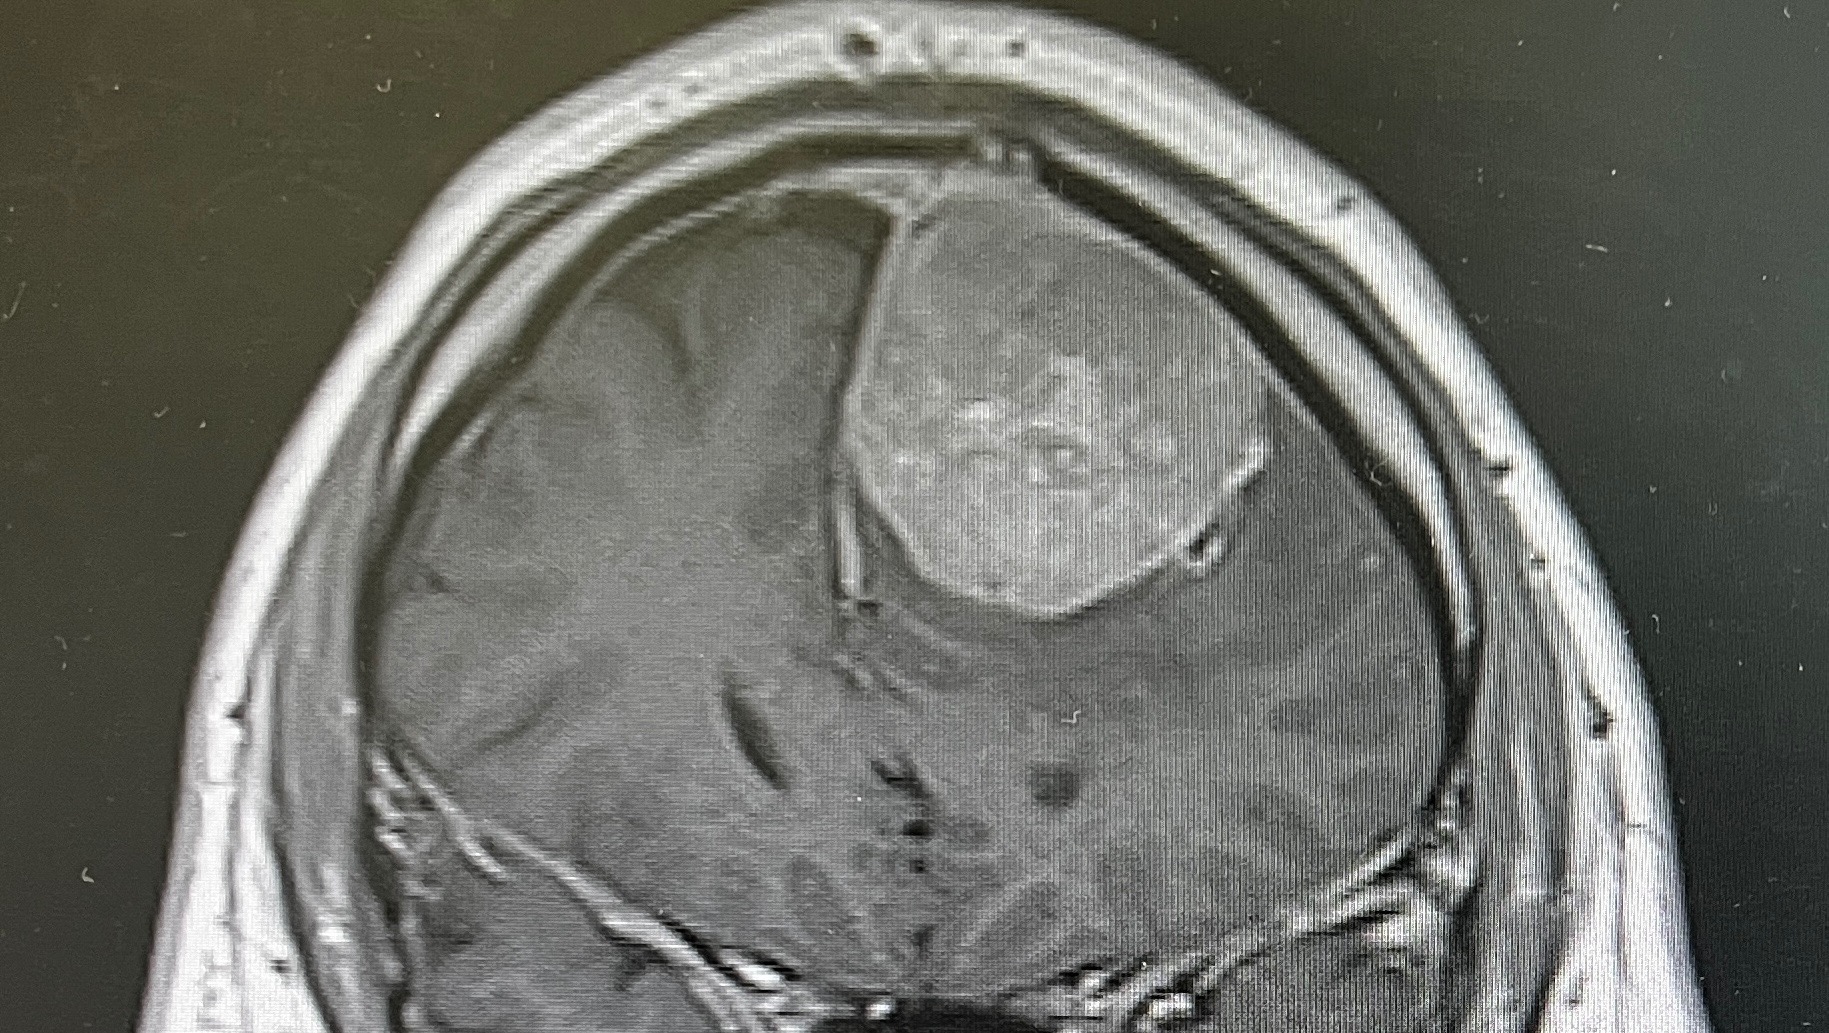

Once in the hospital I was given an MRI where

the neurological team fond a 5x4x4 cm tumor growing inside my left frontal lobe with current blood flow.

The pressure has been extensive and is around 15-20 years old according to the bruised aera and size on the scan.

The mass is not cosmetic or something that can be left untreated. It must have action taken now for my health. .

I have a tumor the size of a small lime to a tennis ball pressing on my left frontal lobe that must come out and I need some confidence it will come out.